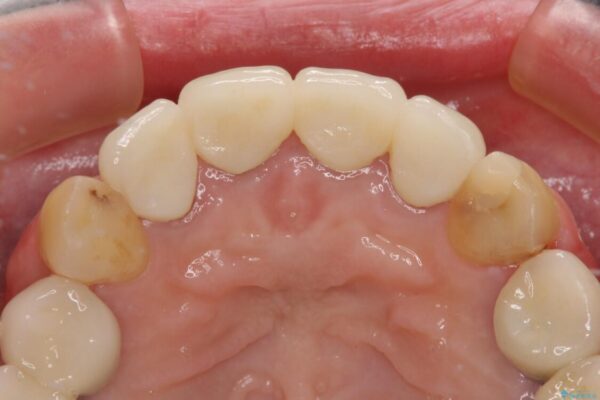

治療後

• 仮歯のまま放置した前歯 オールセラミッククラウンで自然な前歯に 治療後画像

治療後について

日頃の歯磨きをしっかりと行ってくださるので、新しい仮歯に変えてから速やかに歯肉の状態が改善されました。

歯肉からの出血がほとんどないため精度の良い型取りができ、非常に適合の良い補綴治療を行うことができました。